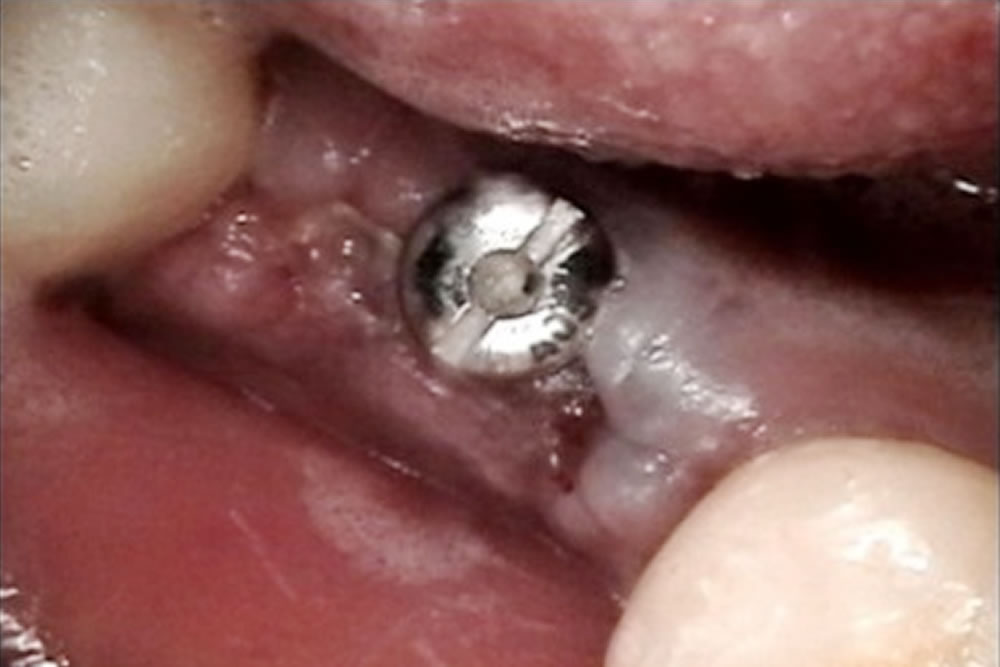

その後、歯茎の形を整えるため、麻酔下でインプラントの頭を出す処置を行いました。

歯茎の形成から3週間後、インプラントの被せ物の型採りを行い、歯型を技工所に送りました。